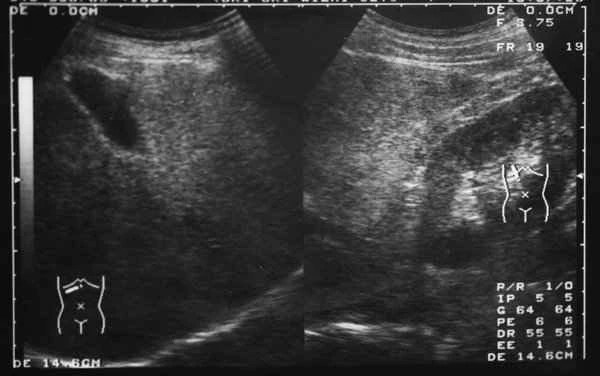

Intestinal obstruction with multiple narrowings in the small intestine

Intestinal obstruction with multiple stenosis of the small intestine refers to a condition in which narrowing occurs in...